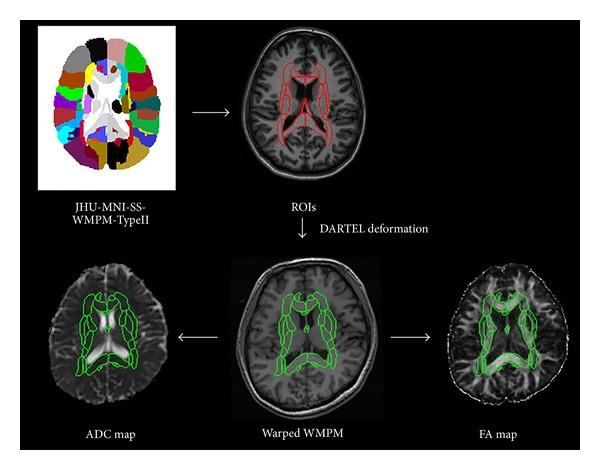

To investigate white matter (WM) abnormalities in neocortical epilepsy, we extract supratentorial WM parameters from raw tensor magnetic resonance images (MRI) with automated region-of-interest (ROI) registrations. Sixteen patients having neocortical seizures with secondarily generalised convulsions and 16 age-matched normal subjects were imaged with high-resolution and diffusion tensor MRIs. Automated demarcation of supratentorial fibers was accomplished with personalized fiber-labeled atlases. From the individual atlases, we observed significant elevation of mean diffusivity (MD) in fornix (cres)/stria terminalis (FX/ST) and sagittal stratum (SS) and a significant difference in fractional anisotropy (FA) among FX/ST, SS, posterior limb of the internal capsule (PLIC), and posterior thalamic radiation (PTR). For patients with early-onset epilepsy, the diffusivities of the SS and the retrolenticular part of the internal capsule were significantly elevated, and the anisotropies of the FX/ST and SS were significantly decreased. In the drug-resistant subgroup, the MDs of SS and PTR and the FAs of SS and PLIC were significantly different. Onset age was positively correlated with increases in FAs of the genu of the corpus callosum. Patients with neocortical seizures and secondary generalisation had microstructural anomalies in WM. The changes in WM are relevant to early onset, progression, and severity of epilepsy.

为了研究新皮质癫痫中的白质(WM)异常,我们通过自动感兴趣区域(ROI)配准从原始张量磁共振图像(MRI)中提取幕上白质参数。对16例患有新皮质癫痫继发全身性惊厥的患者和16例年龄匹配的正常受试者进行了高分辨率和扩散张量MRI成像。使用个性化纤维标记图谱完成幕上纤维的自动划分。从个体图谱中,我们观察到穹窿(cres)/终纹(FX/ST)和矢状层(SS)的平均扩散率(MD)显著升高,并且FX/ST、SS、内囊后肢(PLIC)和丘脑后辐射(PTR)之间的分数各向异性(FA)存在显著差异。对于早发性癫痫患者,SS和内囊豆状核后部的扩散率显著升高,FX/ST和SS的各向异性显著降低。在耐药亚组中,SS和PTR的MD以及SS和PLIC的FA存在显著差异。发病年龄与胼胝体膝部FA的增加呈正相关。患有新皮质癫痫和继发性全身性发作的患者在白质中存在微观结构异常。白质的变化与癫痫的早发、进展和严重程度相关。